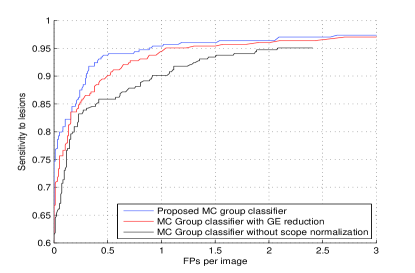

The proposed CAD were first evaluated on a separate GE Senographe projection image dataset with and truthed biopsy-proven malignant MCs and MC groups. The candidate generator provided sensitivity to individual MCs with FPs per image. Figure 3 shows the free-response receiver operating characteristic (FROC) curves of the test set from the outputs of the three pre-trained classifiers.

To test the system robustness with respect to unseen data, all GE projection images and their counterparts with subtracted local means were removed from the training set. This reduced about of all the positive training samples. The FROC in red curve in Figure 3 shows that the system still keeps a high sensitivity rate even with this smaller training dataset.

The black FROC curves were generated from training features without scope-based normalization. Instead, only a global entire breast region based normalization was used for each image. Especially, the FROCs in Figure 3(a) show the strength of the scope-based normalization to increase the robustness of both appearance features and consistency measurement features.